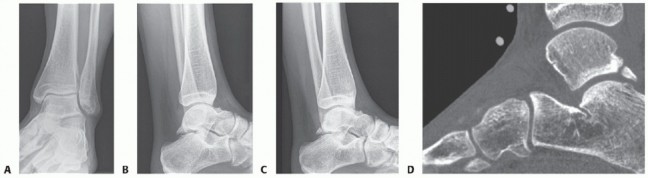

DEFINITION The term osteochondral lesion of the talus (OLT) refers to any pathology of the talar articular ca…

DEFINITION Osteochondral lesions of the talus (OLT) are common conditions that can involve both the cartilage…